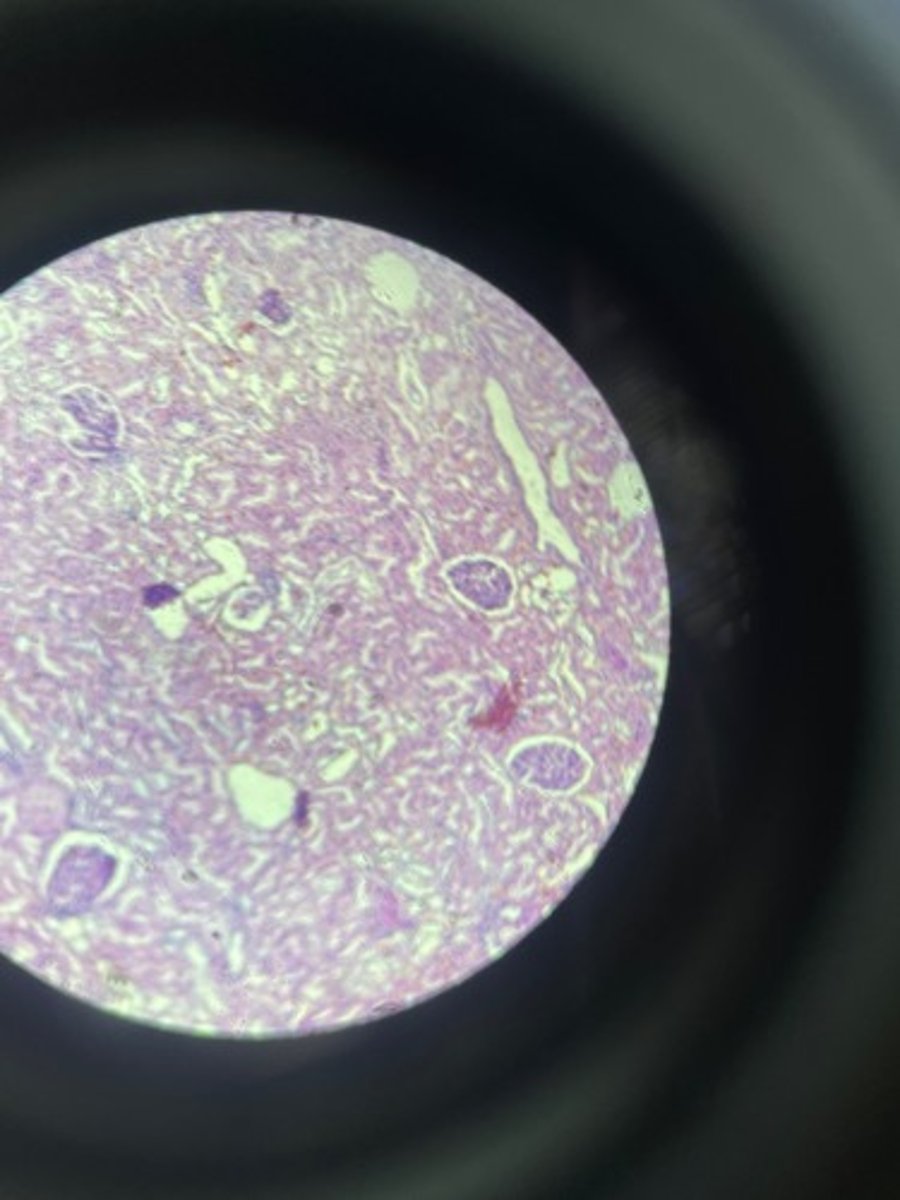

Kidney HE

Kidney HE

Kidney HE

Kidney HE

Kidney HE